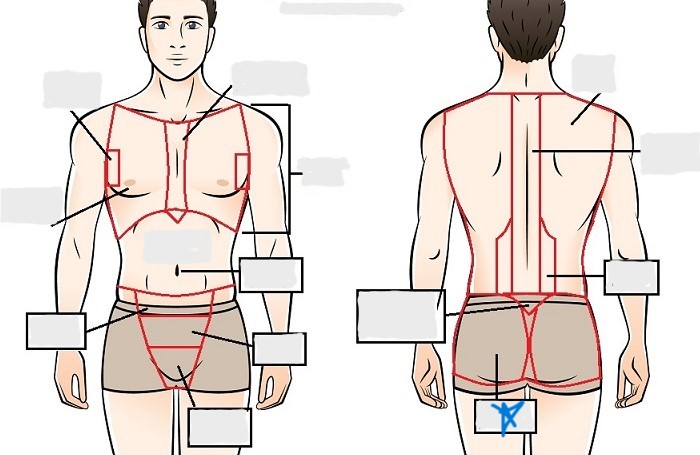

axial

cephalic

occipital

frontal

otic

orbital

nasal

oral

mental

cervical

dorsal

scapular

vertebral

lumbar

sacral

gluteal

thoracic

sternal

mammary

axillary

abdominal

umbilical

pelvic

inguinal

pubic

perineal

appendicular

acromial

brachial

antecubital

olecranal

antebrachial

carpal

manus

coxal

femoral

patellar

popliteal

crural

sural

peroneal

calcaneal

plantar